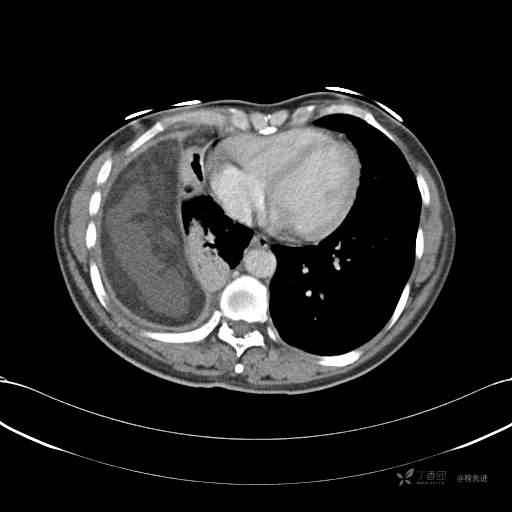

患者性别:女

患者年龄:51岁

简要病史:胸闷半年